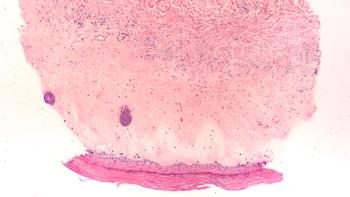

UV exposure or trauma to the skin, such as blistering and ulceration, can lead to changes in skin pigmentation and appearance.